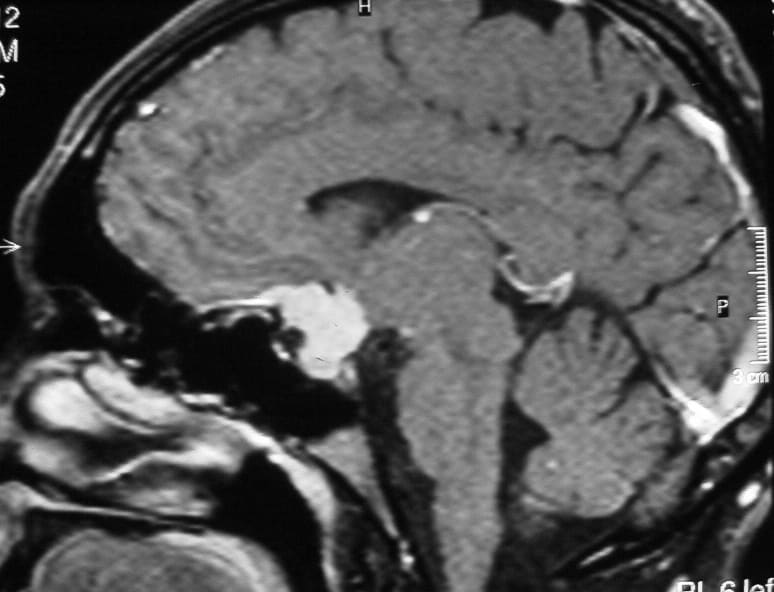

El diagnóstico se puede confirmar y el tumor localizar mediante:

• TAC cerebral

• RM cerebral

• Angiografía cerebral